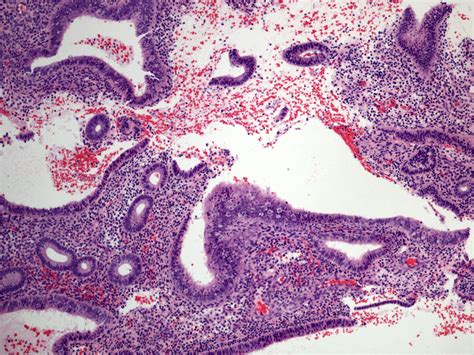

Weakly Proliferative Endometrium refers to a condition where the endometrium does not thicken adequately during the proliferative phase of the menstrual cycle. The proliferative phase is the first half of the menstrual cycle, during which the endometrium prepares for potential implantation of a fertilized egg. In a normal cycle, the endometrium thickens under the influence of estrogen. However, in cases of Weakly Proliferative Endometrium, this thickening is insufficient, which can impact fertility and overall reproductive health.

• Endometrial Biopsy: A small sample of the endometrium is taken for laboratory analysis to evaluate its structure and function.